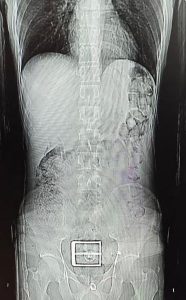

Şüphelinin mide ve bağırsağından uyuşturucu çıktı.

F.S.’nın götürüldüğü hastanede vücudundan 78 kapsül halinde 603,35 gram Afyon sakızı, 17 kapsül halinde 111,35 gram sentetik uyuşturucu çıkarıldı.